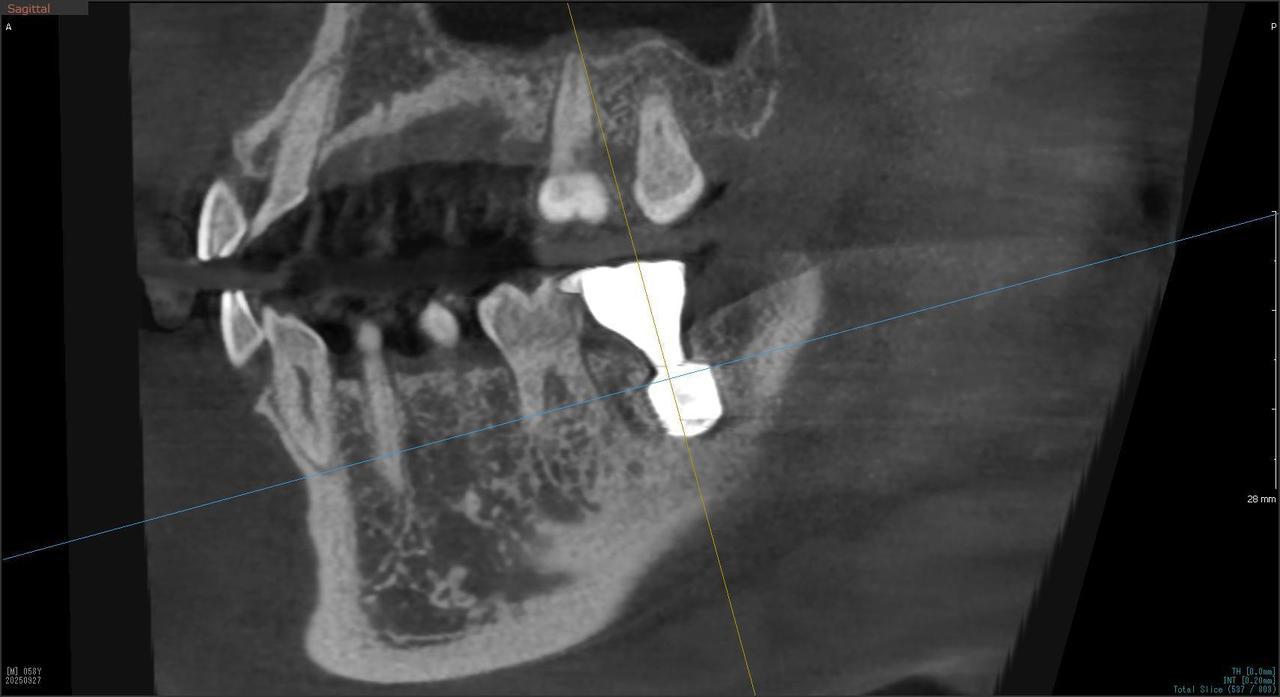

5.左上4番のインプラント抜歯即時埋入、左上6番の上顎既存骨1から2mmのグラフトレスサイナスリフト、左下56の大幅な骨欠損により、下顎神経の損傷を回避するために、ショートインプラントを使用し、左下56にインプラントを埋入し、最終補綴物は、左上456の3ユニットのジルコニアブリッジし、左下56は、ジルコニアの連結冠を装着したケース

Before

枚方市のインプラントの症例

M・I 様 女性 70代

症状としては、左下56は、歯周病で欠損したと考えられるが、かなりの骨欠損をともなっていた。左上456に関しては、動揺が大きく、炎症が起き、排膿、および、歯性上顎洞炎を起こしていた。

治療法としては、動揺がひどくなってきて、炎症の症状もあったため、左上56の抜歯を希望。インプラント治療をその後、希望したため、左上4に関しては抜歯即時埋入。左上6に関しては、既存骨1から2mmでインプラント治療が厳しい状態であったが、グラフトレスサイナスリフトを行い、治療期間5か月はかかるということを説明して、インプラント埋入をおこないました。その後、2か月半後、大幅に骨が欠損している下顎56に対して、ショートインプラントを使用して、下顎神経の損傷を避けて、インプラント埋入を終えています。その後2か月後に光学印象で印象を行い、上顎刺億456歯、3ユニットのジルコニアブリッジを装着。下顎左側56に関しては、骨欠損が大きいため、歯冠長がだいぶ長くなるため、ジルコニアの連結冠を装着して治療を終えた。

治療結果は、上顎6に関しては、既存骨が少なく、厳しい治療ではありましたが、5か月で治療を終え、患者様の負担を最小限に抑えるができたと考えます。(従来のサイナスリフトでは、このようなケースでは1年以上、1年程度の治療期間がかかるか、治療が不可能と言われるケースだと考えます。)また、下顎は骨欠損が大きく、下歯槽管のリスクが起きることが考えられますが、ショートインプラントを使用することで安全に治療を行うことができました。

治療の期間・回数:治療期間5か月(上顎456 3ピースブリッジの治療は5か月(上顎既存骨が2mm程度しかなく、骨結合に時間がかかるケースであったために、5か月の治療期間が必要であった。)(左下56に関しては2か月半で治療を終えています。)治療回数は、13回。

治療の価格:1,474,000円(税込)

治療費の内訳:左上46および左下56のインプラント基本料(フィックスチャー及び手術費用、投薬費用、レントゲン費用、インプラント上部費用(アバットメントおよびジルコニアクラウンの費用用)330000円(税込み)×4本分 1320000円(税込)。左上5ジルコニアポンテック費用88000円(税込)。オプション費用、左上4抜歯即時埋入加算(人工骨費用を含む)+グラフトレスサイナスリフト費用 33000円(税込)、左上6グラフトレスサイナスリフト費用 33000円(税込)

治療のリスクや副作用:手術後に、痛みや腫れ、出血、合併症などを引き起こす可能性があります。噛む感覚がご自身の歯と異なる場合があります。見た目がご自身の歯と異なる場合があります。手術後にメインテナンスを継続しないと、インプラントが抜け落ちる可能性があります。